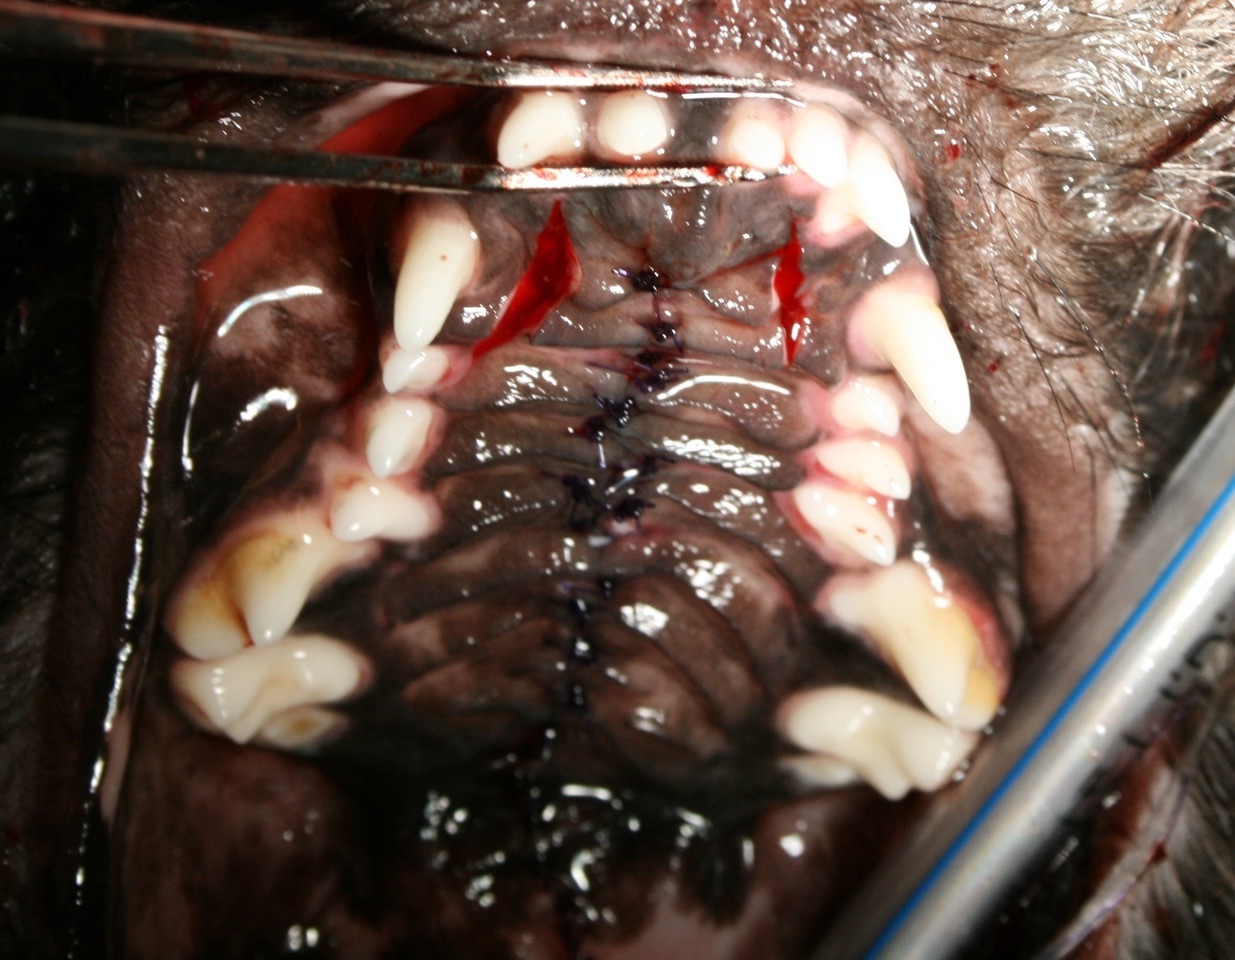

Dr. Martin Florian Buck, Tierarzt

Nach Besprechung der Befunde mit der Besitzerin wurde die Gaumenspalte operativ in der gleichen Narkosesitzung verschlossen. Zuerst wurde die Gaumen-Schleimhaut im Bereich der Gaumenspalte sorgfältig abpräpariert, damit keine Epithelreste eine Wundheilung verhindern können. Bei der Blutstillung wurde auf HF-chirurgische Instrumente verzichtet, um die Blutgefäßversorgung und –integrität nicht negativ zu Beeinflussen. Nachdem die knöchernen Defekte im mittleren Bereich der Gaumenspalte nur sehr dezent waren und genug Schleimhaut zur Verfügung stand konnte auf Maßnahmen zur Mobilisierung weiterer Schleimhaut verzichtet werden. Im rostralen Bereich caudal der Papilla Incisivi mussten Entlastungsschnitte nahe des Margo alveolaris angelegt werden. Dies war notwendig, um die Gingiva des harten Gaumens zu mobilisieren und um einen spannungsfreien Wundverschluss gewährleisten zu können. Im Bereich des weichen Gaumens wurden Inzisionen angelegt und das Gaumensegel neu konstruiert. Die Naht erfolgte jeweils zweischichtig Stoß auf Stoß mit Monoplus 4/0 in Form von Einzelheften.